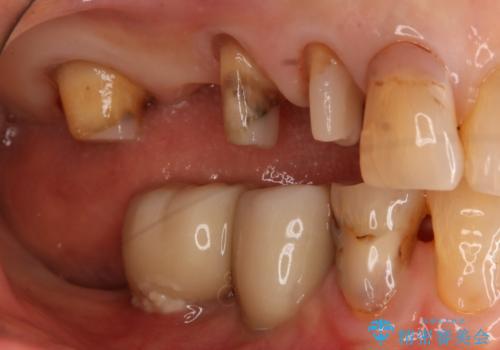

- 数十年前、アメリカで行った治療部位のやり直しを希望されてご来院。

ツギハギの修復が行われてきた被せ物は、縁が合っておらず隙間があり見た目も悪くなってしまっていました。

古い被せ物を除去し、中の状態をキレイにしたうえで改めて金属を使用していない被せ物で噛み合わせの回復を行いました。

被せ物の色は噛み合う反対側の被せ物と合わせて作りました。